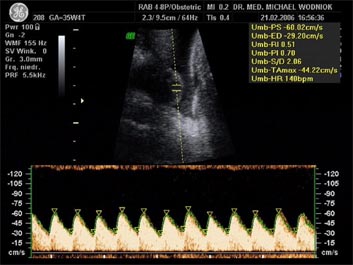

Weitere Ultraschalluntersuchungen sind in der 10./20./30. Schwangerschaftswoche gemäß den Mutterschaftsrichtlinien vorgesehen. Bei erkennbaren Risiken werden  weitere Untersuchungen angeschlossen. Spezielle Ultraschalluntersuchungen zum Ausschluss von kindlichen Entwicklungsstörungen sowie Durchblutungsmessungen der mütterlichen und kindlichen Blutgefäße mittels Farbdopplersonographie gehören zum Leistungsspektrum der Praxis. Auf Wunsch können auch 3D und 4D Untersuchungen angeboten werden.

Blutflußmuster (Nabelschnurarterie)

Mit einer Farbdoppleruntersuchung (Blutflußmessung) der mütterlichen Blutgefäße in der 22. SSW kann überprüft werden ob eine erhöhte Wahrscheinlichkeit besteht, eine Schwangerschaftserkrankung (Gestose) zu entwickeln und ob bei dem  Kind eine Wachstumsverzögerung zu erwarten ist.